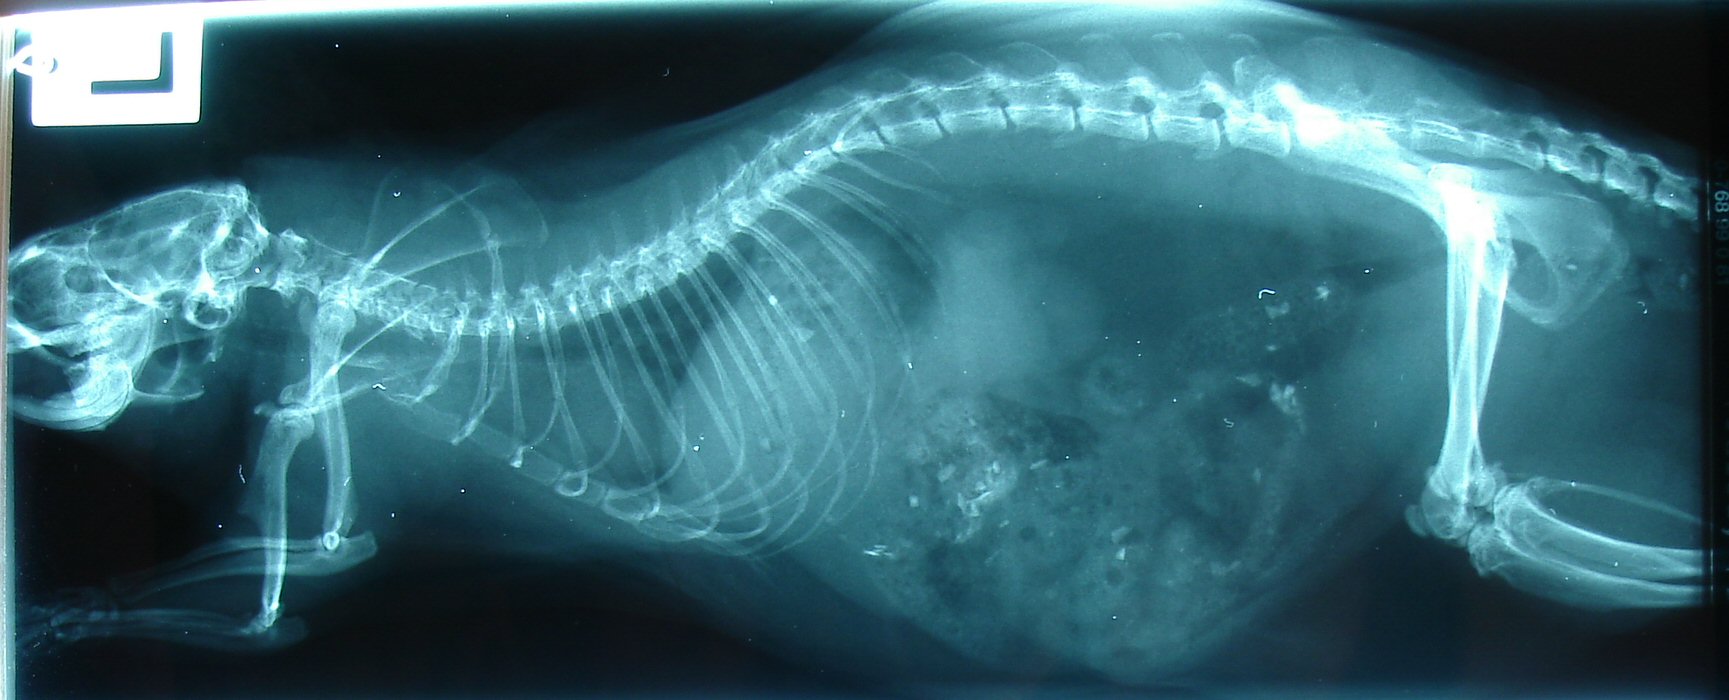

Obduktionsbefund:

Bei der histologischen Untersuchung

fand sich im Gehirn und Rückenmark ein nicht eindeutig

klassifizierbares, invasiv wachsendes, malignes

Blastom. In der Lunge lagen eine hochgradige, akute

Stauungshyperämie, ein mittelgradiges, alveoläres Ödem

und eine gering- bis mittelgradige,

multifokale, subintimale Verkalkung arterieller Gefäße vor.

Beurteilung: die Erkrankungsursache des euthanasierten Tieres besteht

in einem nicht eindeutig klassifizierbaren, invasiv wachsenden,

malignen

Blastom in Gehirn und Rückenmark. Aufgrund des Fehlens von

Tumorzellen in anderen Organen ist von einer primär

intrakraniellen Neoplasie

auszugehen. Sichere Hinweise auf infektiöse Erkrankungen haben

sich nicht ergeben.